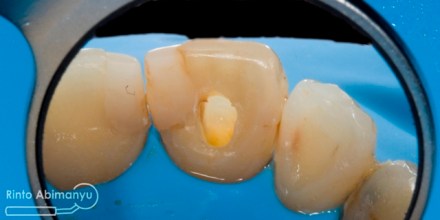

Tambalan lama dibongkar dan seluruh jaringan karies sekunder dibuang, kemudian tepi kavitas labial dibuatkan bevel…

Setelah tambalan dibongkar dan dibuatkan bevel

Gigi-gigi kemudian dietsa dan dibonding, penambalan menggunakan resin komposit Palfique LX5 (Tokuyama) shade OPA2, OA3, A3… Pada kasus ini saya tidak memakai cetakan silikon untuk membantu membentuk outline gigi, hanya mengandalkan seluloid strip..